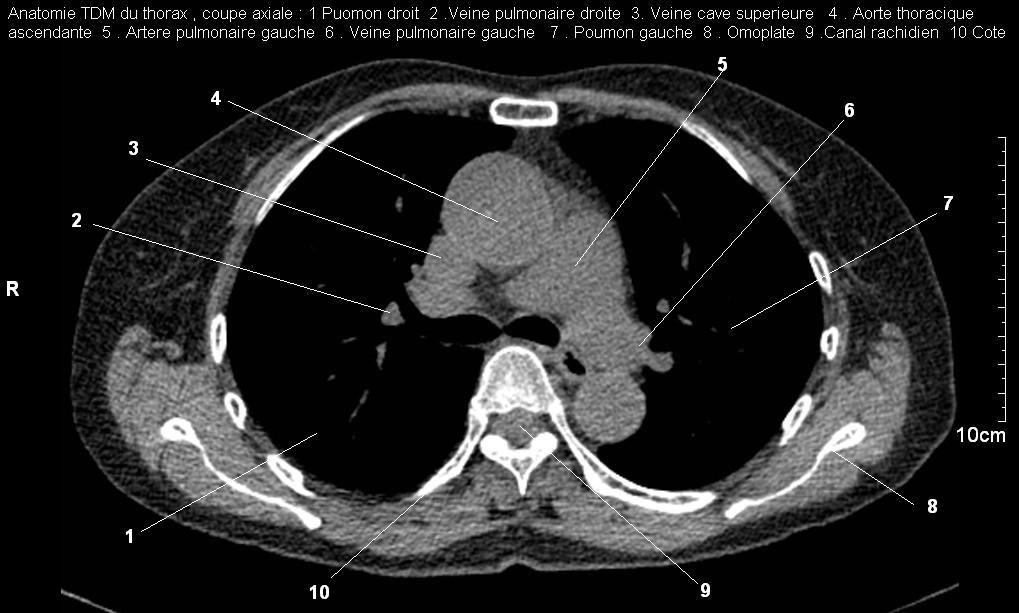

Radioanatomie pulmonaire ( image radiologie thoracique normale )- La Tomodensitometrie du  thorax ( coupes axiales fenetre mediastinale )

Les fenetres mediastinales permettre d'etudier anatomie du mediastin , les structures vasculaires en coupes axiales de 0,5-1cm sur le thorax . Ceux qui s'installent  travers le thorax de C4 a L1, L2 a n'a pas de contrast et se donnent des resutats suivantes :